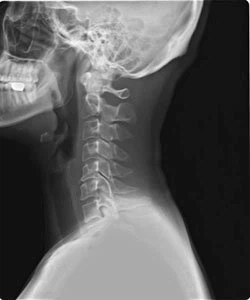

오늘 건강 정보는 목디스크 증상과 원인에 대해 알아보고 목디스크에 좋은 운동을 소개드리겠습니다. X-ray로 목을 촬영해보면 목뼈가 c 곡선을 유지하는 것이 정상이라고 합니다. 하지만 휴대전화와 태블릿을 사용함으로써 머리를 숙이고, 책상 앞에 앉아 책을 보는 시간이 많거나, 잘못된 자세를 취하고 있다면 목뼈의 배열이 흐트러지는 경우가 많습니다.

목을 받쳐주는 뼈를 경추라고 하는데 여기는 뼈가 7개 있고 이 뼈 마디마다 디스크라는 것이 있습니다. 이 디스크의 역할은 척추 뼈 사이에 충격을 완화하고 운동할 수 있게 합니다. 목디스크는 퇴행성 척추 질환으로 목 주위 근육, 인대가 장기간 압력을 받고 퇴행하여, 디스크가 자신의 역할을 하지 못하고 밀려나고 통증과 같은 목디스크 증상을 보이는 질병입니다.